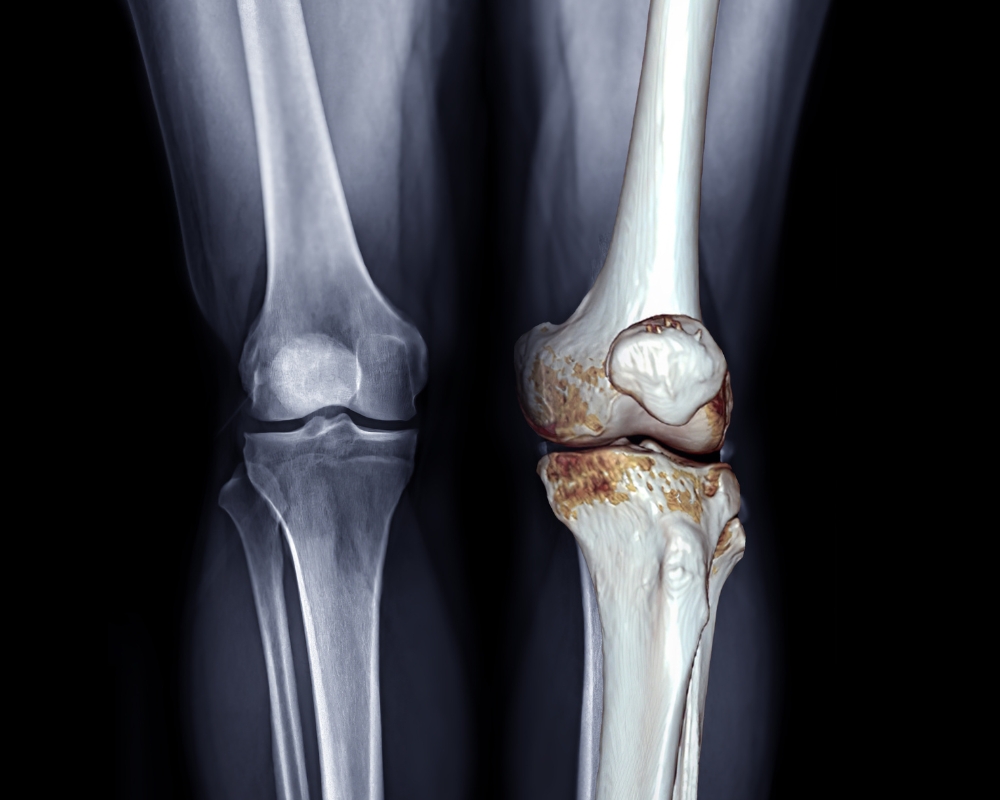

Hình ảnh thoái hóa khớp gối

Thoái hóa khớp gối là bệnh lý mãn tính, thường gặp ở người lớn tuổi, nhưng hiện nay đang có xu hướng trẻ hóa ở những người 20 - 30 tuổi. Bệnh phản ánh tình trạng sụn khớp bao bọc đầu khớp bị bào mòn, dẫn đến hai đầu xương cọ xát vào nhau gây đau, viêm và hạn chế vận động.

Thoái hóa khớp gối tiến triển qua 04 giai đoạn chính, mỗi giai đoạn có những đặc điểm khác nhau trên lâm sàng và hình ảnh X-quang: